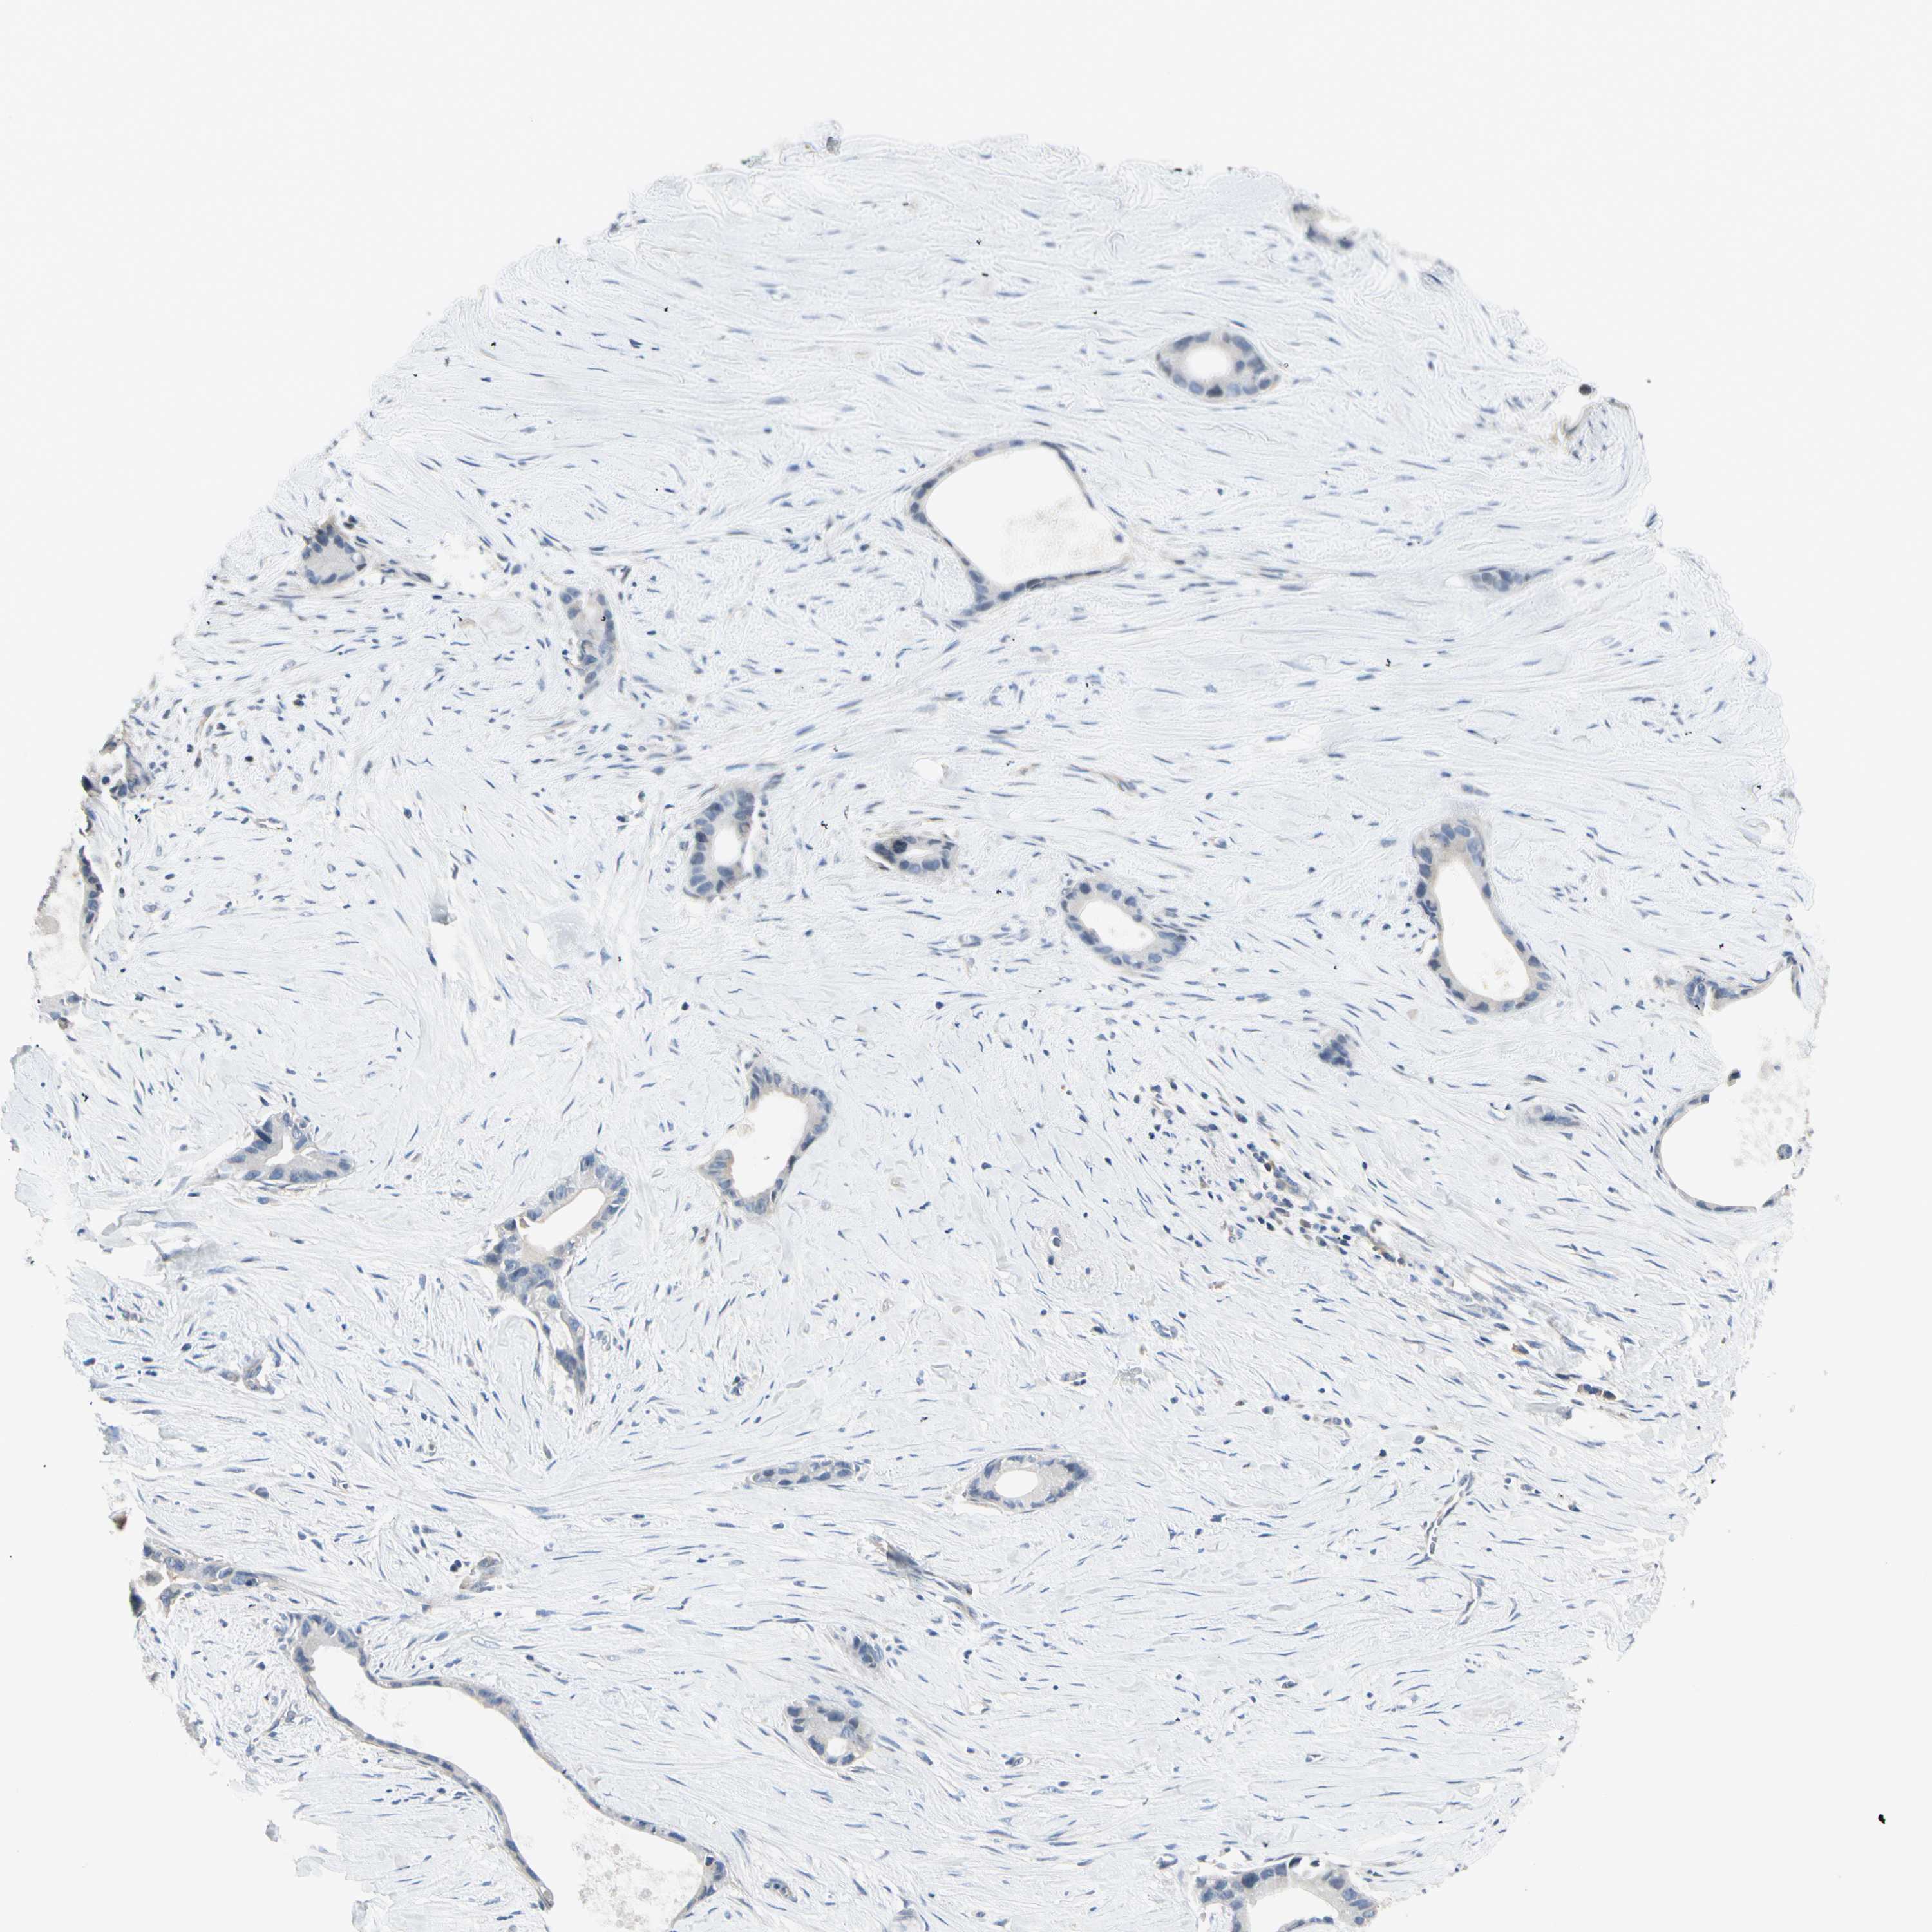

LIVER CANCER - Protein expressioni

A mouse-over function shows sample information and annotation data. Click on an image to view it in a full screen mode. Samples can be filtered based on level of antibody staining by selecting one or several of the following categories: high, medium, low and not detected. The assay and annotation is described here.

Note that samples used for immunohistochemistry by the Human Protein Atlas do not correspond to samples in the TCGA dataset.

Antibody stainingi

Antibody staining in the annotated cell types in the current human tissue is reported as not detected, low, medium, or high, based on conventional immunohistochemistry profiling in selected tissues. This score is based on the combination of the staining intensity and fraction of stained cells.

Each image is clickable and will lead to virtual microscopy that enables deeper exploration of all samples and also displays staining intensity scores, fraction scores and subcellular localization as well as patient and tissue information for each sample.

Antibody HPA007159

Staining

High

Medium

Low

Not detected

Intensity

Strong

Moderate

Weak

Negative

Quantity

>75%

75%-25%

<25%

None

Location

Nuclear

Cytoplasmic/membranous

Cytoplasmic/membranous,nuclear

Cholangiocarcinoma

Carcinoma, Hepatocellular, NOS